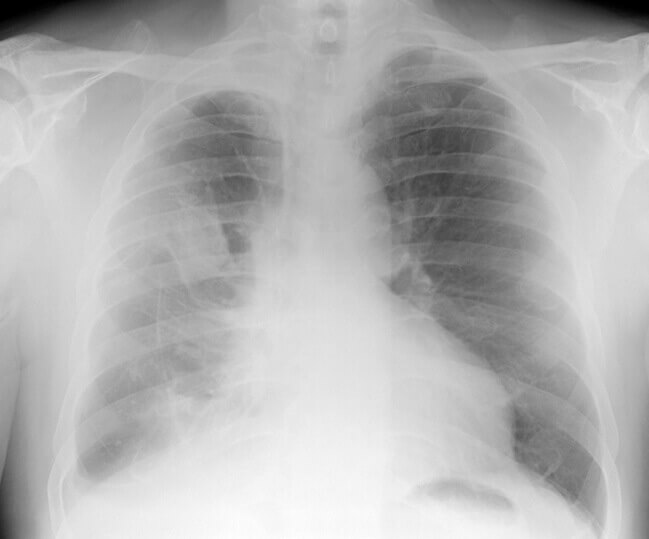

From www.gettyimages.com

Extensive Right Mesothelioma On A Chest Xray From Asbestos Exposure What Does Mesothelioma Chest Pain Feel Like Overview symptoms and causes diagnosis. Common mesothelioma symptoms include chest and abdominal pain, coughing and fluid. pain pain is a common symptom of mesothelioma. malignant pleural mesothelioma (affecting the chest and lungs) is the most common type. the main symptoms of mesothelioma of the lungs are shortness of breath and chest pain. Tell your doctors or specialist. What Does Mesothelioma Chest Pain Feel Like.